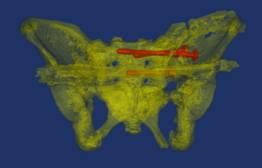

模拟置钉和术后钉道